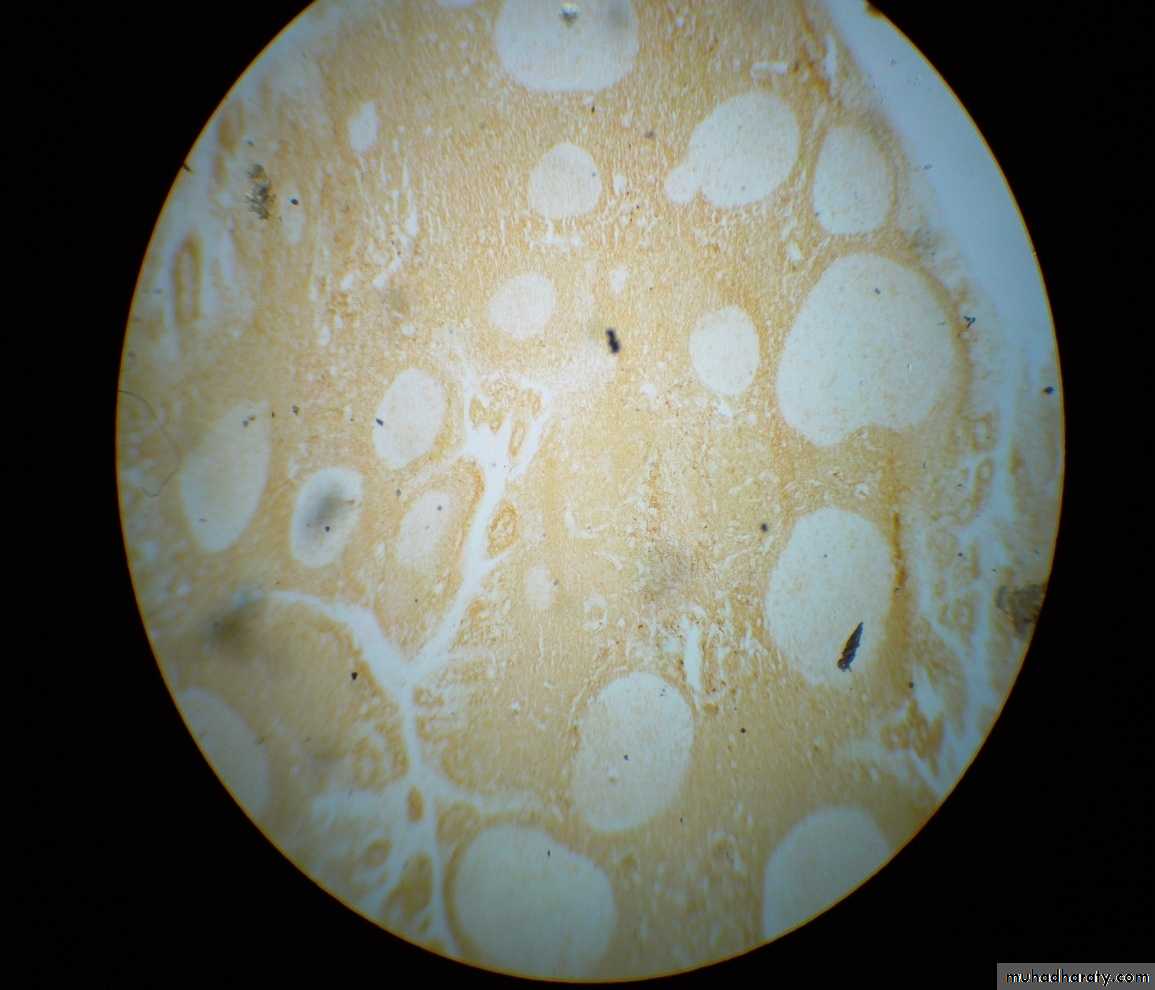

T cell markers: CD3 or CD4

1ry follicles : Few cells are positive

2ry follicles:M.Z: Few cells are positive

G.C: Few cells are positive

- IFA : Majority of cells are positive (2/3 of the cell population)

CD3 can not be differentiated from CD4 from this slideT cell markers: CD8

1ry follicles : Few cells are positive2ry follicles:

M.Z: Few cells are positiveG.C: Few cells are positive

- IFA : Minority of cells are positive (1/3 of the cell population)